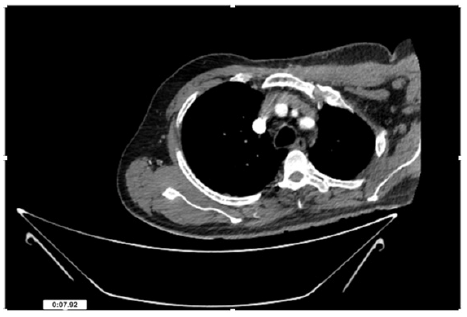

55-years-old chronic smoker had acute, severe pain in the right upper limb for one week; it was cold upto mid arm with skin discoloration. He also noticed numbness and weakness of movement of elbow joint. He underwent below elbow amputation in February 2023 for acute ischemia of left upper limb. He was a current chronic smoker; 15 pack year. General condition was weak; temperature was normal; blood pressure was 100/60mmHg; heart rate was 92/minutes with sinus rhythm; SpO2 was 97% on air; heart was normal. In lower extremities, all peripheral pulses were intact. Local Examination of right upper limb revealed as follows: tenderness; coldness; discoloration; decreased motor function and sensory modalities. Axillary, brachial and radial pulses were not palpable. Hand-held Doppler failed to detect any signal in arterial system; therefore, we arranged for emergency embolectomy. complete occlusion of right upper limb arterial system Full blood count showed high hemoglobin (14.6gm%); normal total WBC and platelet count. Coagulation profile was normal. Parenteral unfractionated heparin, antibiotics, tramadol, proton-pump inhibitors, anti-platelets and HMG CoA reductase inhibitors were given. Doppler ultrasound demonstrated complete occlusion of right upper limb arterial system. CT Angiogram illustrated occlusion of subclavian artery downwards on both sides. Figures 1-14 shows complete occlusion of right subclavian artery without collaterals. On Day ‘2’ of admission, the patient passed black tarry stool for 3 times. However, the vital signs were stable; blood pressure was 100/60mmHg; heart rate was 92/min; SpO2 was 97% on air; the abdomen was soft and not tender. Above elbow amputation was done on Day ‘2’ of admission. Intra-operative findings were as follows: (1) no active bleeding at brachial artery; (2) thrombosis along brachial artery; (3) muscle color and consistency were not healthy.

Figure 4: CT Angiogram at neck showing normal brachio-cephalic trunk, common carotid artery, and narrow right subclavian artery.

Figure 5: CT Angiogram at neck showing normal brachio-cephalic trunk, common carotid artery, and narrow right subclavian artery.

Figure 6: CT Angiogram at neck showing brachio-cephalic trunk, common carotid artery and narrow right subclavian artery.

Figure 7: CT Angiogram at neck showing brachio-cephalic trunk, common carotid artery and narrow right subclavian artery.

Figure 10: CT Angiogram at upper arm showing totally occluded right axillary artery; normal internal carotid artery and external carotid artery.